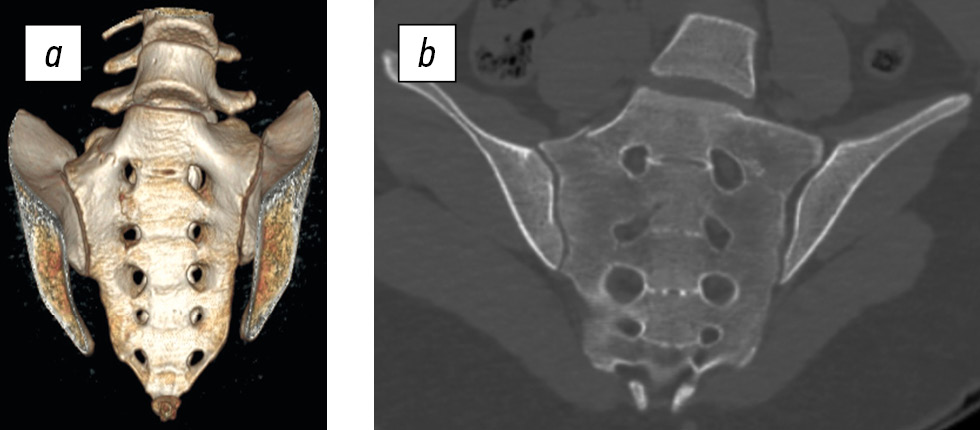

Fig. 1. Three-dimensional reconstruction (a) and CT scan (b) of the lower thoracic and lumbar spine, pelvic bones, and hip joints of a 16-year-old female patient. Subtype IIIb injury of the left side of the pelvis (acetabular and iliac wing fractures). Transitional lumbosacral vertebra, subtype IIa.

The subtype IIa presented in Fig. 1 is characterized by an enlarged transverse process (either left, as in this case, or right) of the vertebra above the sacrum, which articulates with the sacral ala via a pseudoarticulation [11].